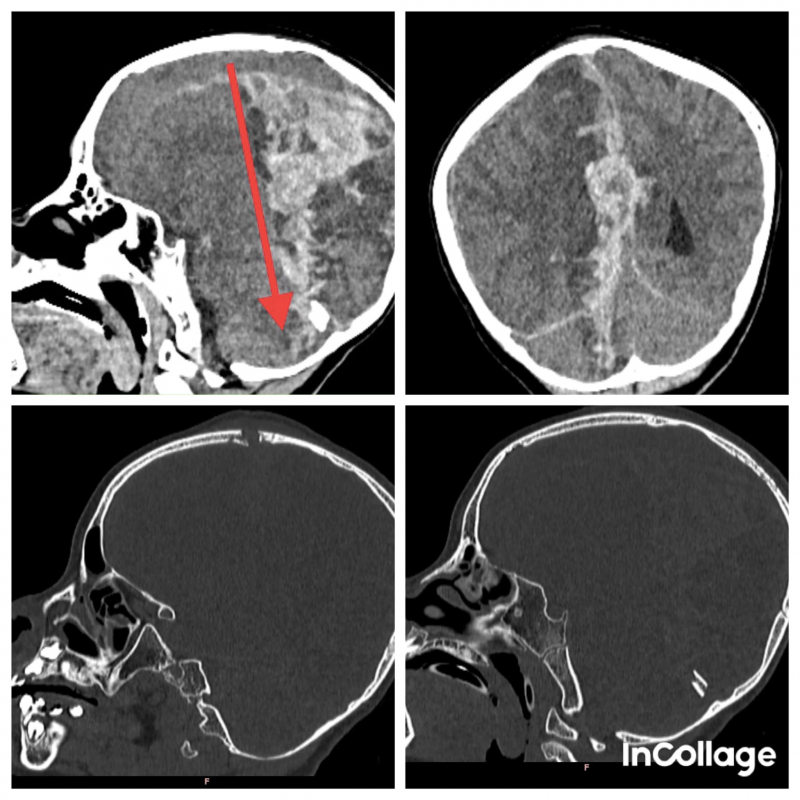

Bé B.T.Y.N. (SN 2017, ngụ tại Bình Phước) được bệnh viện tuyến dưới chuyển đến Bệnh viện Nhi Đồng 2 trong tình trạng hôn mê sâu, có vết thương trước đỉnh đầu đã được khâu. Kết quả CT-Scan ghi nhận tổn thương xuyên thấu qua não từ phía trước đỉnh đầu xuyên ra đến phần tiểu não phía sau, gây xuất huyết dưới màng cứng và trong não lượng nhiều, chèn ép và phù não.